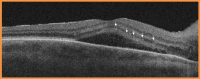

Figure 2. Optical coherence tomography (OCT) showed macular oedema at the onset of ocular symptoms

OCT examination revealed right eye intra-retinal and sub-retinal fluid and multiple hyperreflective inner retinal round foci in inflammation (arrows)